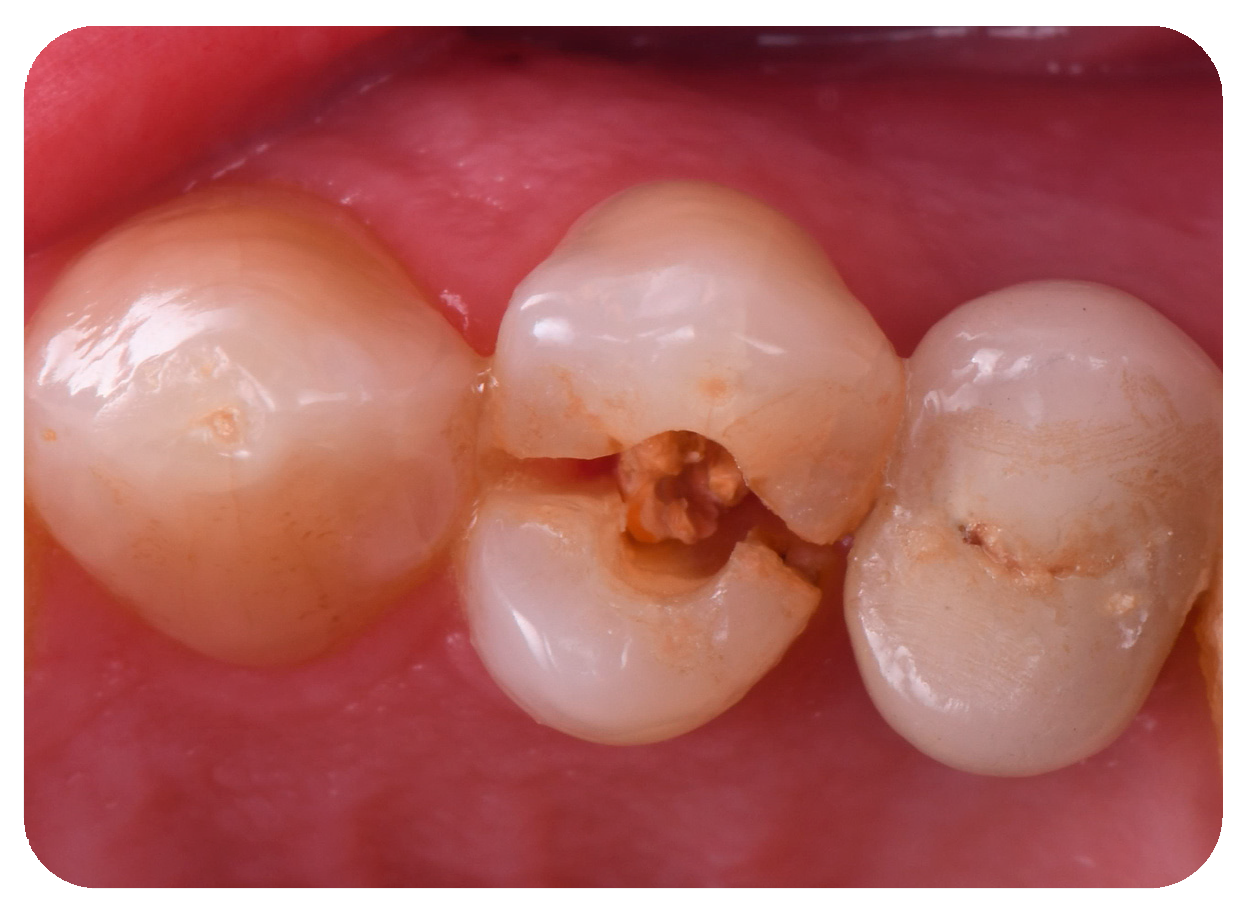

2. Case Presentation

2.1. Clinical Procedures